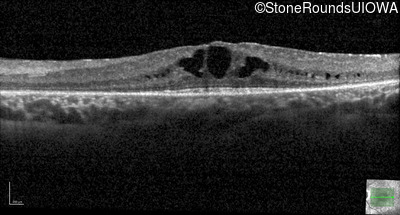

Optical Coherence Tomography - Right - 20/40

Exemplar / OCT Stack

OCT Stack